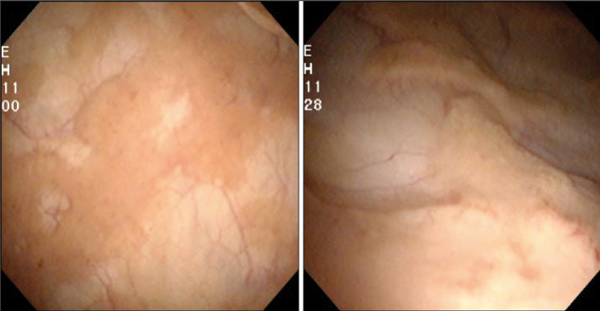

A 55 year-old female presented with persistent E.coli urinary tract infections (UTI). She underwent cystoscopy and the following lesion was identified.

Figure 1.

Figure 2.

(Images reproduced from Korean J Urogenit Tract Infect Inflamm 2013;8(2):125-8.

Copyright © 2013, Korean Association of Urogenital Tract Infection and Inflammation.)

- Describe the lesion seen on figure 1. What is the likely cause?

- What pathognomonic histological feature is seen in figure 2?

Soft, raised, pale yellow plaques on the bladder mucosa. Malakoplakia - associated with defective macrophage function.

Michaelis-Gutmann bodies. Represent remnants of phagosomes mineralised by iron and calcium deposition.